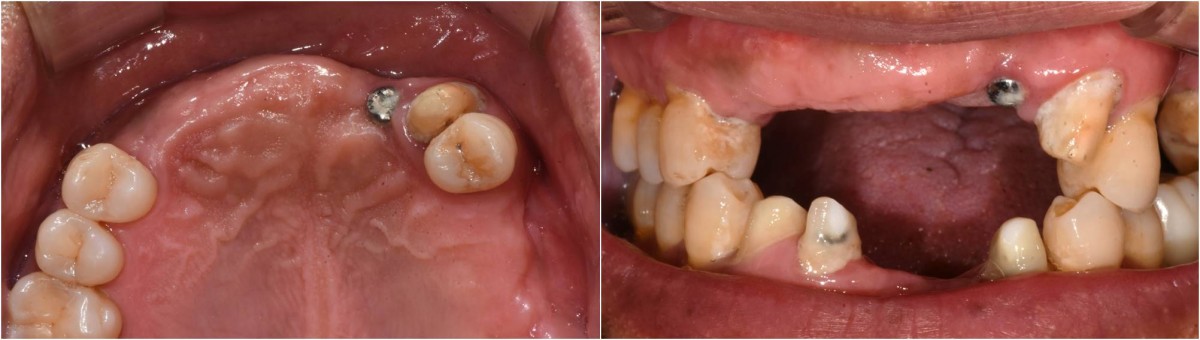

<GCpbc> A 58-year-old male is a patient undergoing implant installation in various parts. The old Br of the anterior maxilla has fallen

off and it is no longer possible to maintain it even temporarily, so a

treatment plan for the anterior teeth was made.